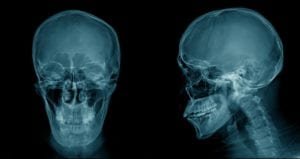

Front and side view of a skull x-ray imageFirst, we should clear up an issue about terms. A word like “mild” in connection with TBI is by its very nature vague and unhelpful.